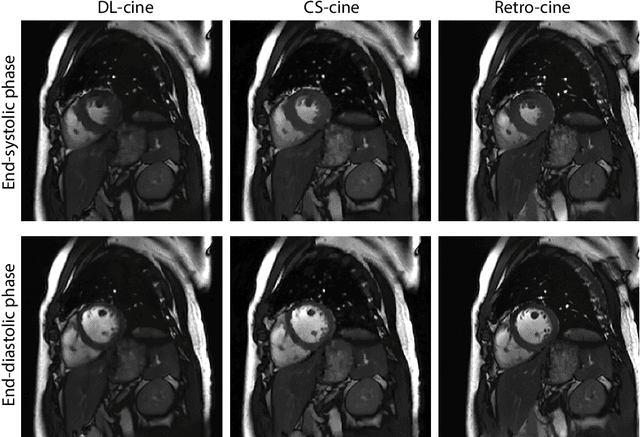

Abstract:Retrospectively gated cine (retro-cine) MRI is the clinical standard for cardiac functional analysis. Deep learning (DL) based methods have been proposed for the reconstruction of highly undersampled MRI data and show superior image quality and magnitude faster reconstruction time than CS-based methods. Nevertheless, it remains unclear whether DL reconstruction is suitable for cardiac function analysis. To address this question, in this study we evaluate and compare the cardiac functional values (EDV, ESV and EF for LV and RV, respectively) obtained from highly accelerated MRI acquisition using DL based reconstruction algorithm (DL-cine) with values from CS-cine and conventional retro-cine. To the best of our knowledge, this is the first work to evaluate the cine MRI with deep learning reconstruction for cardiac function analysis and compare it with other conventional methods. The cardiac functional values obtained from cine MRI with deep learning reconstruction are consistent with values from clinical standard retro-cine MRI.